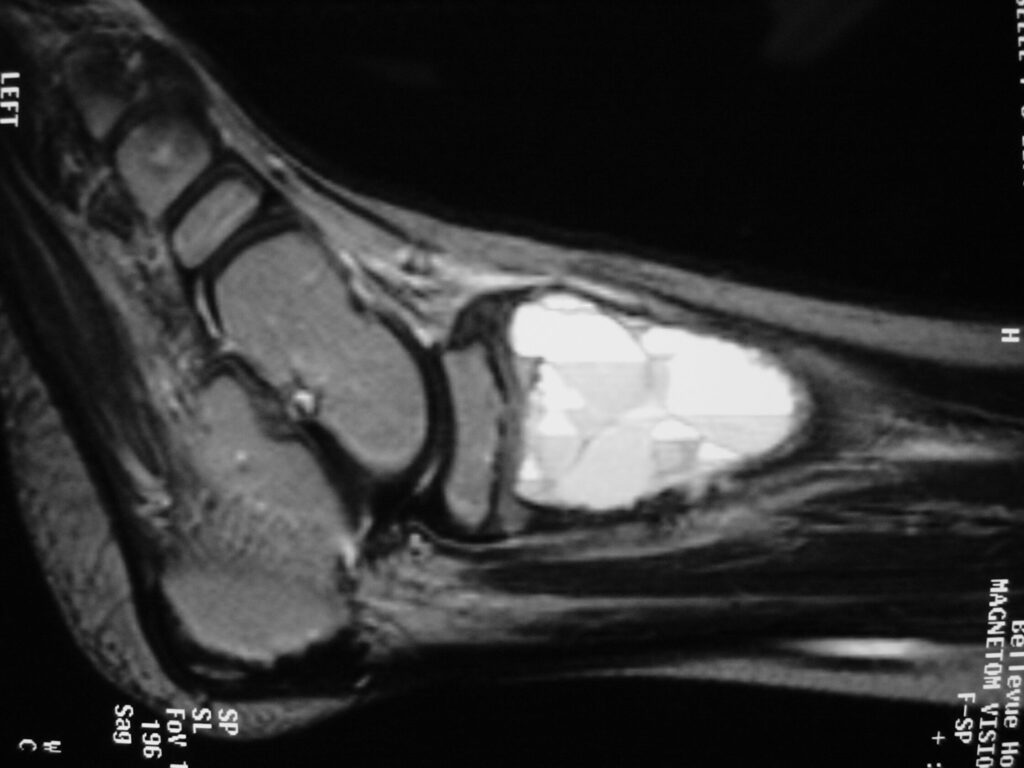

MRI

- Geographic well circumscribed

- High signal on T2 weighted MRI images

- Fluid/Fluid level (T2) are highly characteristic

Fig 2 a-e. MRI of an ABC of Distal Tibia: Fig 2 a-c: geographic cystic expansile lesion with fluid-fluid levels. The fluid-fluid levels are caused by bleeding into the cavities. The blood collects and the degredation products settle to the gravity dependent areas of the cavities. This shows up as fluid-fluid levels on the MRI. Fig 2 d,e: This is a gadolinium enhanced MRI of the ABC of the distal tibia. There is peripheral and septal enhancement indication cyst formation. The contrast outlines the cystic cavities but does not enter into the center

Fig 2 a: Coronal T2 weighted MRI of an ABC

Fig 2b: Sagittal T2 weighted MRI of and ABC

Fig 2c: Axial T2 weighted MRI of an ABC

Fig 2d: Coronal gadolinium enhanced MRI of an ABC

Fig 2e: Sagittal gadolinium enhanced MRI of an ABC